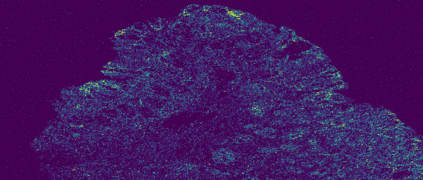

The usage of chemical imaging technologies is becoming a routine accompaniment to traditional methods in pathology. Significant technological advances have developed these next generation techniques to provide rich, spatially resolved, multidimensional chemical images. The rise of digital pathology has significantly enhanced the synergy of these imaging modalities with optical microscopy and immunohistochemistry, enhancing our understanding of the biological mechanisms and progression of diseases. Techniques such as imaging mass cytometry provide labelled multidimensional (multiplex) images of specific components used in conjunction with digital pathology techniques. These powerful techniques generate a wealth of high dimensional data that create significant challenges in data analysis. Unsupervised methods such as clustering are an attractive way to analyse these data, however, they require the selection of parameters such as the number of clusters. Here we propose a methodology to estimate the number of clusters in an automatic data-driven manner using a deep sparse autoencoder to embed the data into a lower dimensional space. We compute the density of regions in the embedded space, the majority of which are empty, enabling the high density regions to be detected as outliers and provide an estimate for the number of clusters. This framework provides a fully unsupervised and data-driven method to analyse multidimensional data. In this work we demonstrate our method using 45 multiplex imaging mass cytometry datasets. Moreover, our model is trained using only one of the datasets and the learned embedding is applied to the remaining 44 images providing an efficient process for data analysis. Finally, we demonstrate the high computational efficiency of our method which is two orders of magnitude faster than estimating via computing the sum squared distances as a function of cluster number.